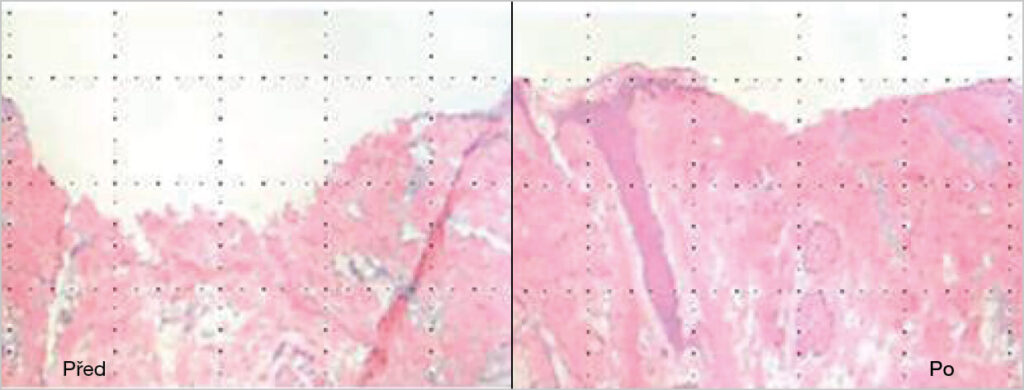

Unikátní kombinace aktivních látek v séru Vermione GHA přináší komplexní péči o pleť. Podporuje přirozenou obnovu a regeneraci buněk, zlepšuje jas a vitalitu pokožky a přispívá k jejímu celkovému vyhlazení.

Sérum pomáhá redukovat jemné, mimické i hlubší vrásky, včetně nosoretních rýh často vznikajících vlivem kouření. Současně napomáhá zjemnění pórů a sjednocení struktury pleti.

Díky své receptuře je sérum účinnou alternativou k invazivním metodám, přičemž zajišťuje dlouhodobý komfort a svěží vzhled. Je vhodné pro všechny typy pleti bez ohledu na věk.